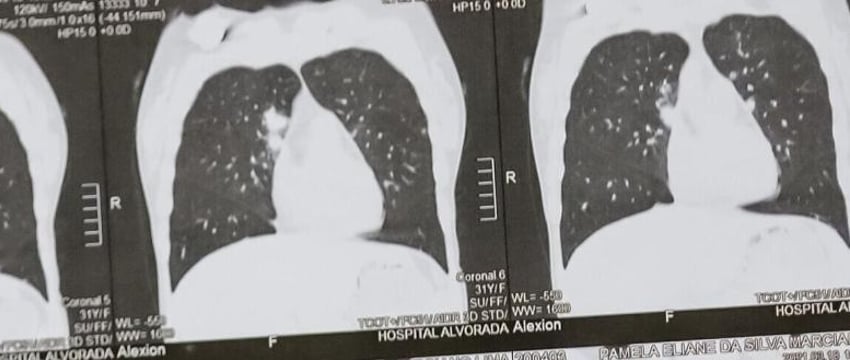

Выявить EVALI очень легко при помощи компьютерной томографии, так как в легких курильщика происходят патологические изменения.